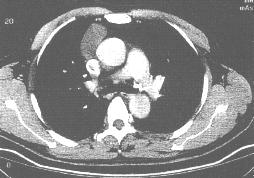

其他輔助檢查:1.氣管支氣管囊腫 胸部X 線檢查常見隆突附近邊界清楚、質地均勻的縱隔內腫物,多為圓形或卵圓形,隨呼吸運動其形狀可發生變化。亦可見於縱隔內其他部位。一般無分葉,無鈣化。隆突下的囊腫可使隆突角度增大。食管旁的囊腫鋇餐檢查可見食管有明顯受壓。與氣道相通而繼發感染者可見囊腫在短期內擴大,可出現氣液平面。胸部CT 掃描可以明確囊腫的位置及其與周圍結構的關係,典型的囊腫呈圓形或卵圓形,CT 值為0~20HU,囊壁十分菲薄;囊腔內液體含蛋白量高時CT 值升高,反覆慢性感染者囊壁可以增厚。

4.心包囊腫 胸部X 線檢查見心包囊腫通常位於前縱隔心膈角區,但也有位置較高者,少數患者可延伸至上縱隔區,右側明顯較左側多見。囊腫輪廓清楚光滑,密度均勻,一般無鈣化影。有時在側位胸片可見囊腫呈水滴狀上尖下圓的陰影,可能為囊腫嵌入葉間裂所形成,具有一定的特徵性。大多數囊腫直徑為3cm~8cm 之間,但也有小至lcm 和大至28cm 的報導。CT 檢查有助於明確陰影的囊性結構,對位於不典型部位者診斷價值更高。透視下囊腫的形態可隨體位變動和呼吸動作而有變化。